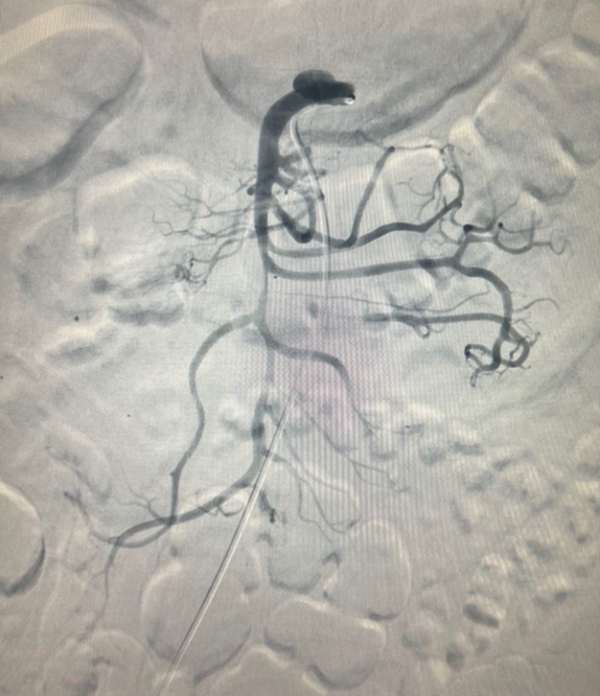

![]() |

| Hình ảnh chụp và can thiệp đặt stent động mạch mạc treo tràng trên: Trước can thiệp bóc tách gần gốc xuất phát, tạo huyết khối gây hẹp lòng và tắc vài nhánh nuôi ruột (hình trái); sau can thiệp đặt stent động mạch mạc treo tái thông hoàn toàn mạch mạc treo, cải thiện tưới máu ruột (hình phải) - Ảnh BVCC |